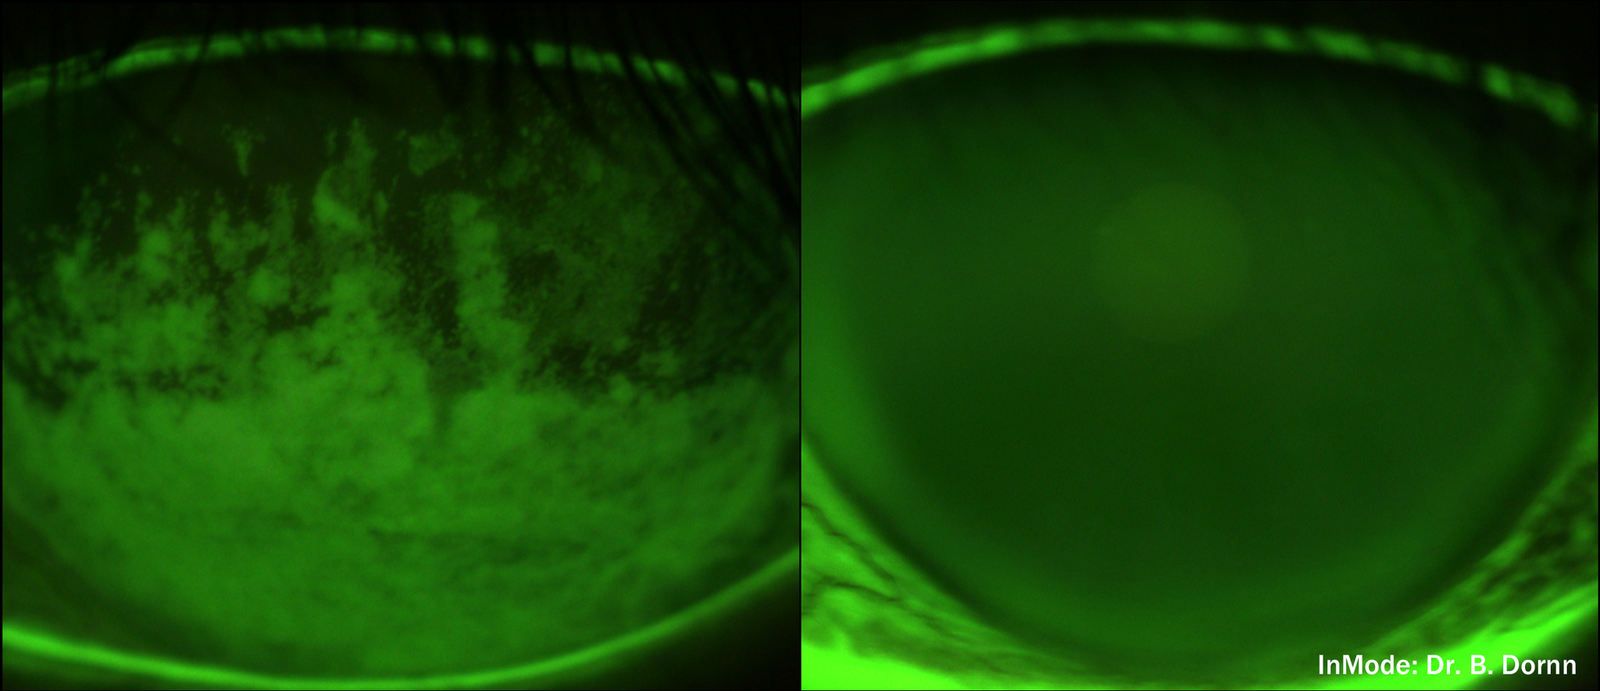

the tears on the left break up or dissipate easily in an uneven fashion. after treatment, tear film on the right is smooth creating clearer, more comfortable eyes and vision